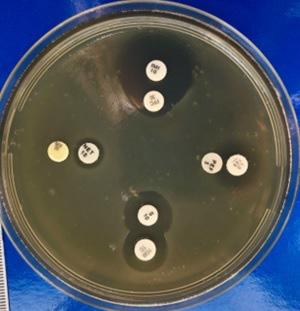

aFigura 1 (a, b). Colonii de P. aeruginosa pe mediu Mueller-Hinton (foto original)

Figura 3 (a, b). S. maltophilia, placa 1, seria 1, antibiotice individuale (foto originale)

Pentru placa 1 cu S. maltophilia (Fig. 3), din cadrul primei serii, s-au dovedit active următoarele antibiotice, în ordinea descrescătoare a eficacității: Marbofloxacina, Kanamicina, Ofloxacina, Lincocin forte, Rifampicina și Neomicina. Pentru Spiramicină și Penicilină s-a constatat fenomenul de antibiorezistență.

Tabelul 1. Zonele de inhibiție a plăcii 1, seria 1, S. maltophilia

Tabelul 2. Zonele de inhibiție a plăcii 1, seria 1, P. aeruginosa

Nr. crt. Antibiotic Zonă de inhibiție

Neomicină 8 mm

Marbofloxacină R

Lincocin forte 15 mm

Spiramicină R

Rifampicină R

Penicilină R

Ofloxacină R

Kanamicină 18 mm Nr. crt. Antibiotic Zonă de inhibiție 1 Neomicină 10 mm 2 Marbofloxacină 21 mm 3 Lincocin forte 18 mm 4 Spiramicină R 5 Rifampicină 15 mm 6 Penicilină R 7 Ofloxacină 18 mm 8 Kanamicină 20 mm

toarele antibiotice, în ordinea descrescătoare a eficacității: Minocyclina, Tobramicina și Netilmicina, Lincocin, Pefloxacina, Streptomicina și Metropenem. Pentru Rifampicină s-a constatat fenomenul de antibiorezistență.

Tabelul 3. Zonele de inhibiție a plăcii 2, seria 2, S. maltophilia

Pentru placa 1 cu P. aeruginosa (Fig. 4), din cadrul primei serii, s-au dovedit active următoarele antibiotice, în ordinea descrescătoare a eficacității: Kanamicină, Lincocin forte, Marbofloxacină și Neomicină. Pentru Spiramicină, Rifampicină, Ofloxacină și Penicilină s-a constatat fenomenul de antibiorezistență.